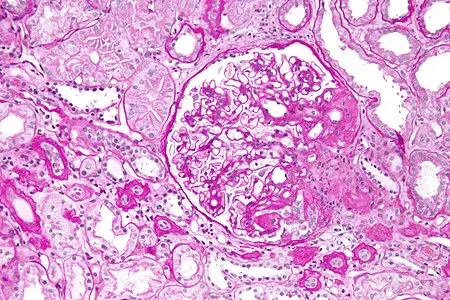

Promessa no tratamento da GESF em pacientes com genótipo APOL1 de alto risco

Promessa no tratamento da GESF em pacientes com genótipo APOL1 de alto riscoValkercyo Feitosa